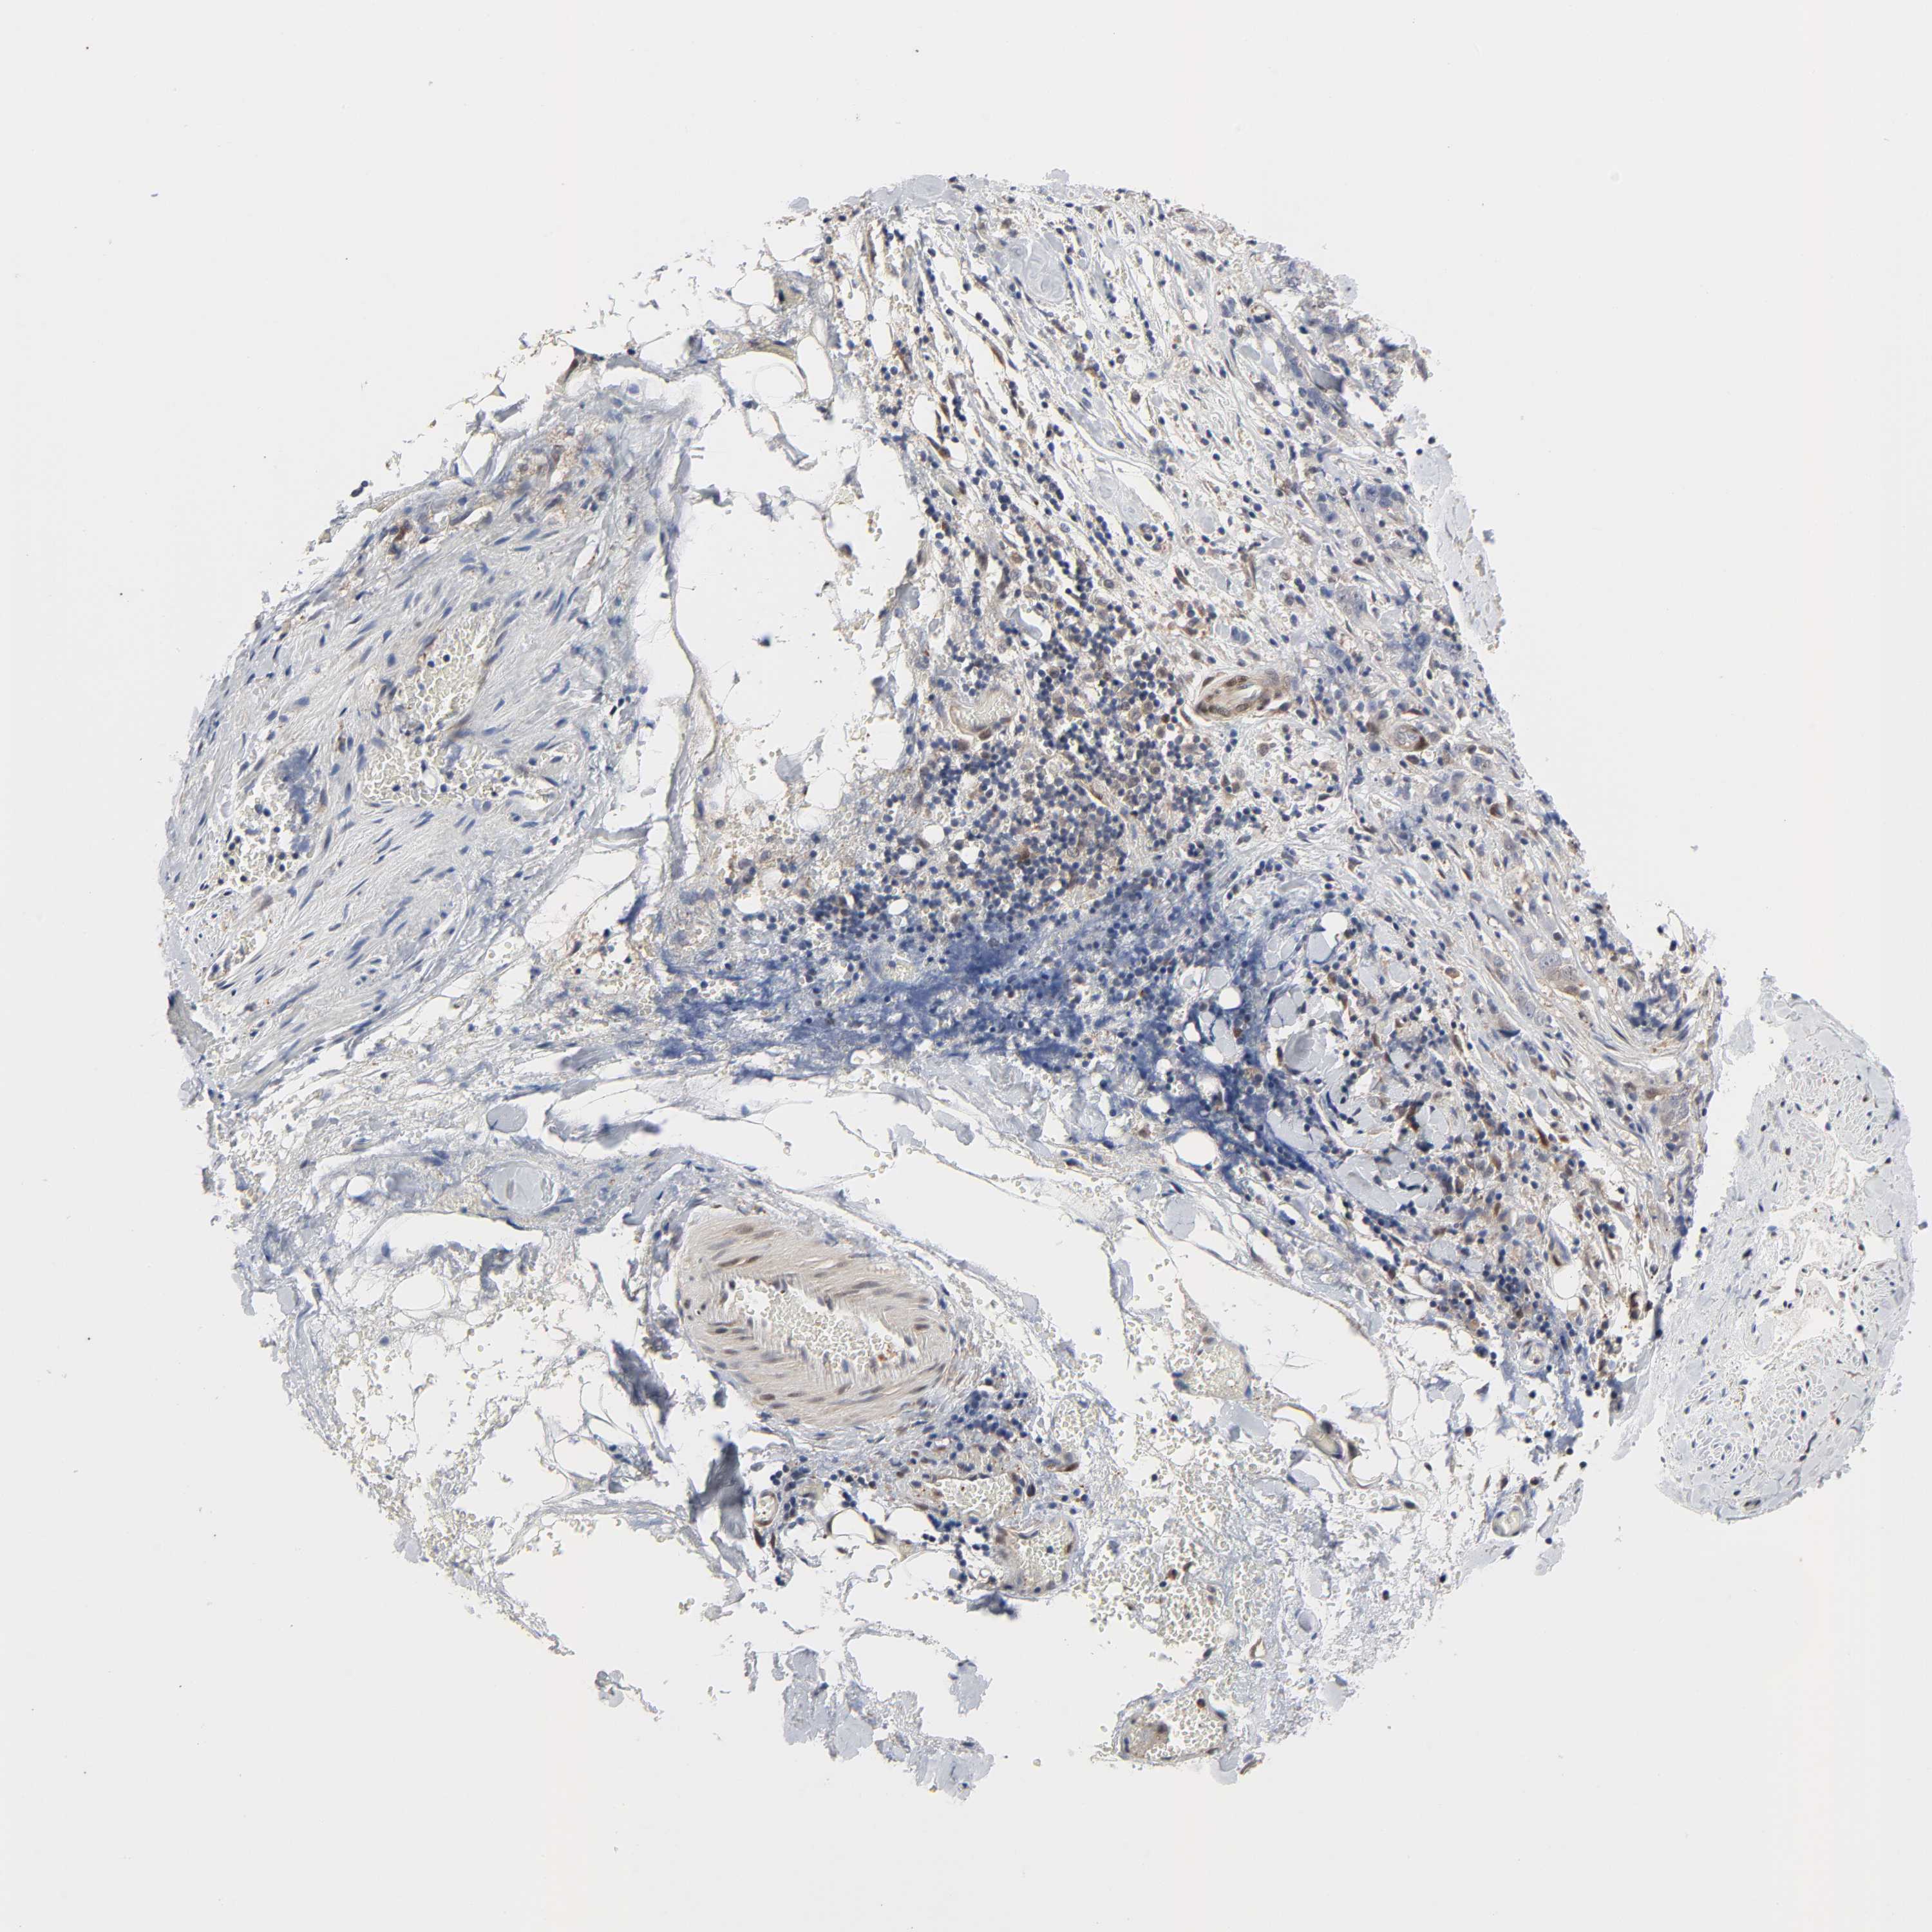

STOMACH CANCER - Protein expressioni

A mouse-over function shows sample information and annotation data. Click on an image to view it in a full screen mode. Samples can be filtered based on level of antibody staining by selecting one or several of the following categories: high, medium, low and not detected. The assay and annotation is described here.

Note that samples used for immunohistochemistry by the Human Protein Atlas do not correspond to samples in the TCGA dataset.

Antibody stainingi

Antibody staining in the annotated cell types in the current human tissue is reported as not detected, low, medium, or high, based on conventional immunohistochemistry profiling in selected tissues. This score is based on the combination of the staining intensity and fraction of stained cells.

Each image is clickable and will lead to virtual microscopy that enables deeper exploration of all samples and also displays staining intensity scores, fraction scores and subcellular localization as well as patient and tissue information for each sample.

Antibody HPA031335

Antibody CAB004076

Antibody CAB080153

Antibody CAB080157

Staining

High

Medium

Low

Not detected

Intensity

Strong

Moderate

Weak

Negative

Quantity

>75%

75%-25%

<25%

None

Location

Nuclear

Cytoplasmic/membranous

Cytoplasmic/membranous,nuclear

Adenocarcinoma, NOS

Adenocarcinoma, High grade